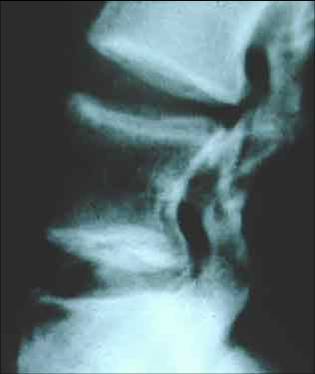

Radiologic finding?

DIagnosis?

Short Lumbar Pedicles

Achondroplasia